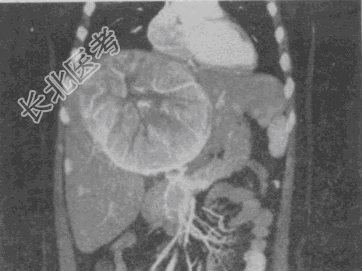

- 单项选择题男,54岁, 有乙肝病史,现腹胀, 右上腹痛,消化不良, 消瘦、乏力、贫血、黄疸,血清转氨酶升高, 白蛋白/球蛋白比值倒置,CT、MRI检查如图, 最可能的诊断是

C、原发性肝癌